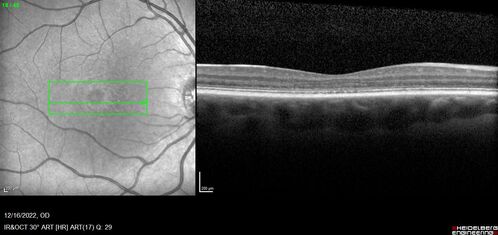

Stargardt Disease - Very Mild - 24 year old

This patient has 3 different ABCA4 mutations. His mother and sister have stargardts and his father has RP. His sisters images are also on Retinagallery.com